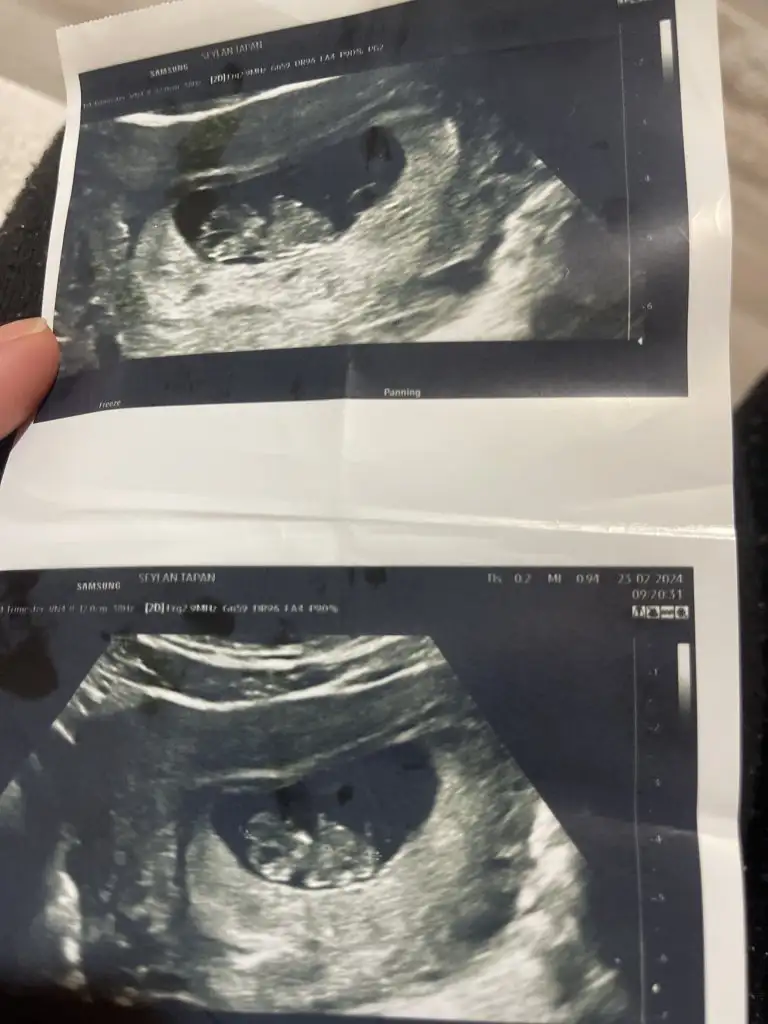

Slm kızlar 9haftalık sizce cınsıyet kızmı erkekmı fıkrınız 😅😅

Eklentiler

• image.webp

image.webp

32,1 KB · Görüntüleme: 234